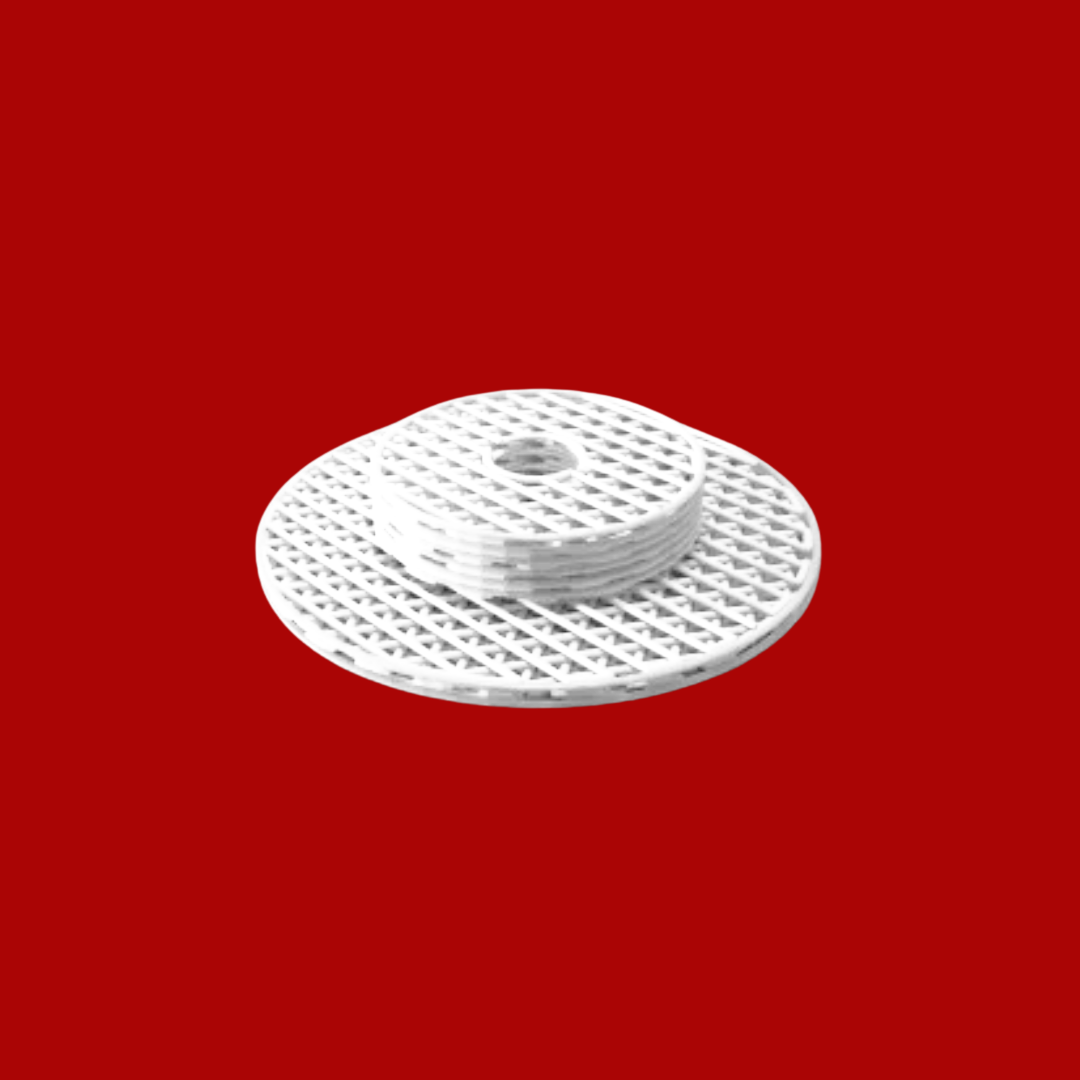

Bloocell® is the world’s first “ARTIFICIAL TISSUE TECHNOLOGY” developed in the field of tissue engineering for the treatment of tissue deficiencies. It is a complementary and therapeutic solution that can be manufactured in patient-specific anatomical forms. With its innovative technology, Bloocell® has become the first legal representative of this paradigm worldwide.Clinical results have been consistently successful. Bloocell® is a three-dimensional scaffold designed for the treatment of damaged or missing tissues. It offers a holistic therapeutic approach by supporting cell growth, tissue formation, and the healing process. While reinforcing the tissue structure, Bloocell® also facilitates cell proliferation and differentiation in an optimized environment. Made from biologically compatible materials, Bloocell® does not induce adverse immune responses once integrated into the body. As a bioresorbable scaffold, Bloocell® is gradually absorbed and replaced by new tissue. This process provides an ideal environment for natural tissue regeneration and repair. Bloocell® can reconstruct various tissue types such as bone, cartilage, soft tissue, skin, and nerves. Therefore, Bloocell® offers a broader application range than grafts and carries lower associated risks.